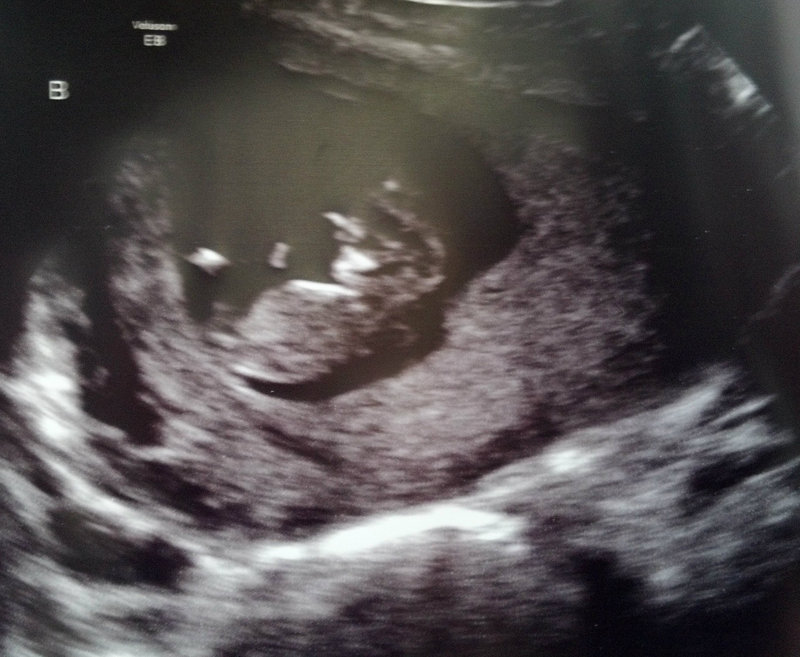

BABY B

Attachment 3159